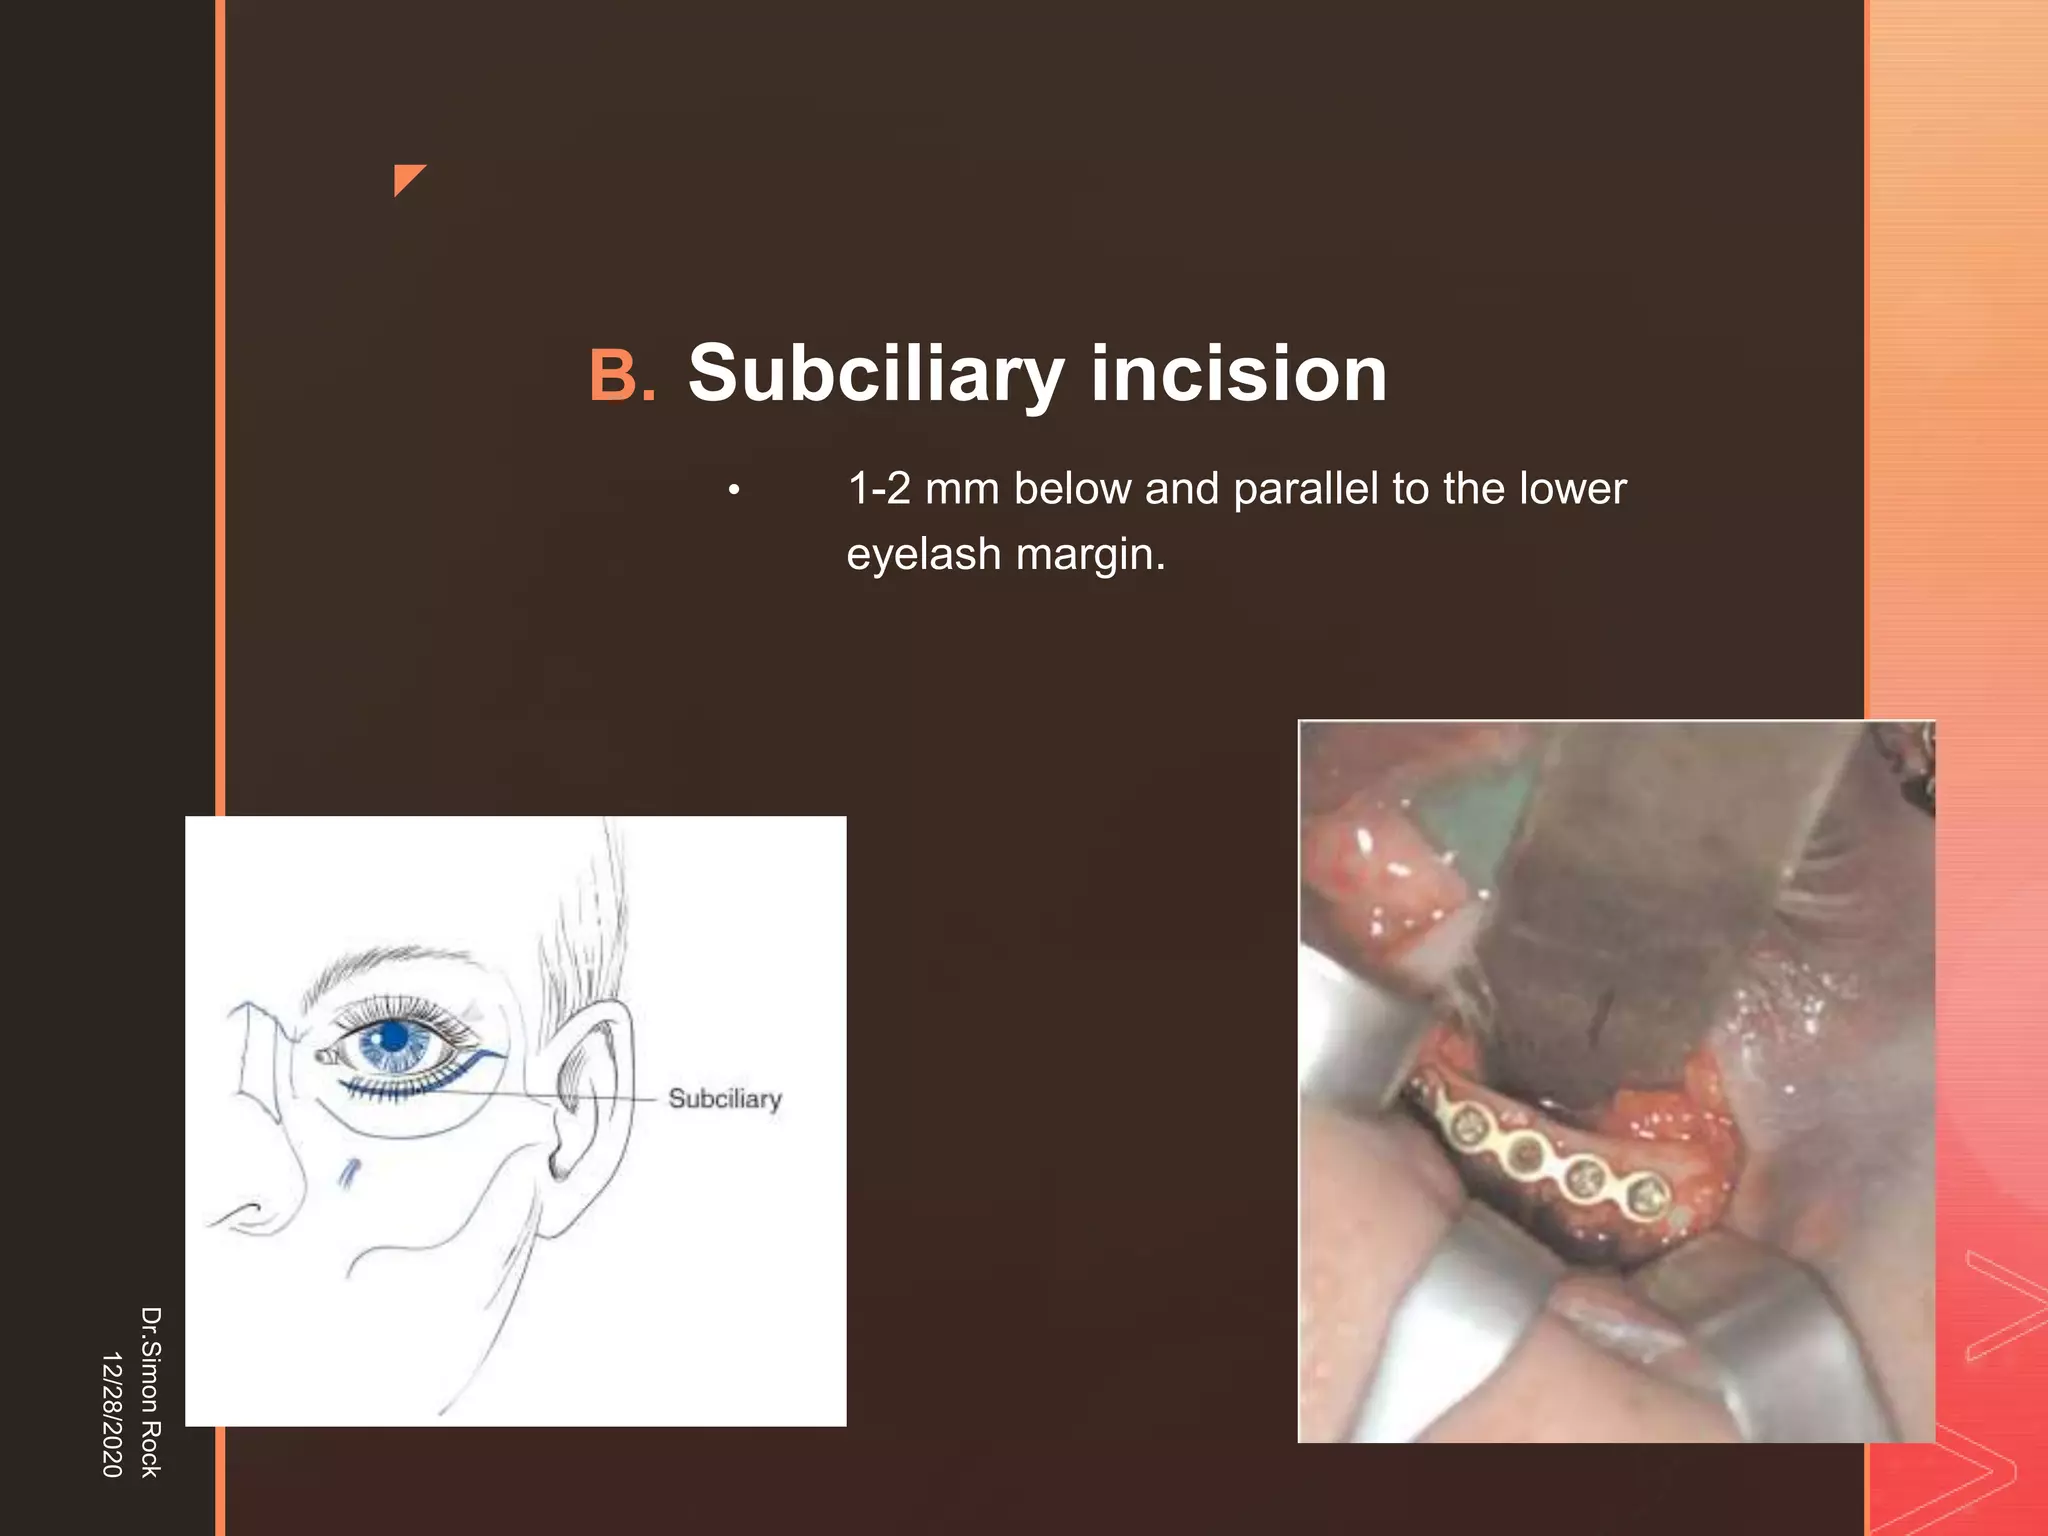

This document discusses the anatomy and fractures of the zygomatic bone. It notes that the zygoma forms the cheekbone and articulates with several other facial bones. Zygomatic fractures most commonly occur in the arch or body due to blunt trauma. Diagnosis involves checking for diplopia, ecchymosis, and other signs of orbital or facial bone involvement. Treatment may involve closed or open reduction based on the severity of displacement. Closed reduction techniques try to elevate the bone back into position without surgery, while open reduction requires surgical exposure and fixation of the fracture site.